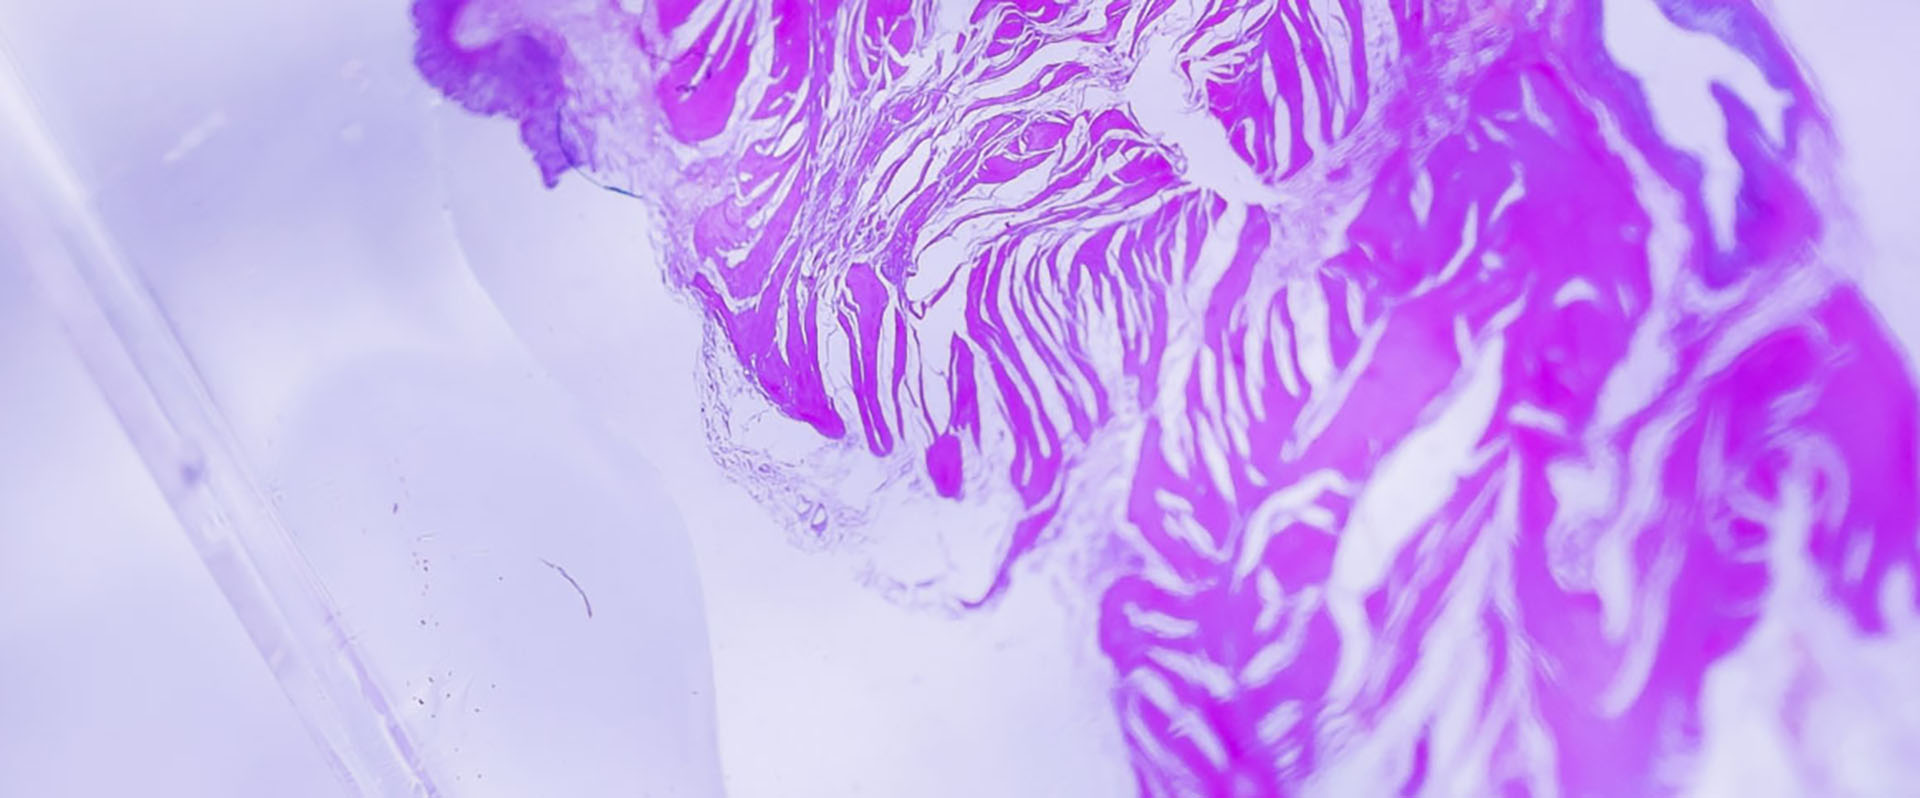

Human biospecimens are our specialty

As a provider of human tissues and liquid samples, we reliably supply the life sciences industry with biospecimens for research and development and create individual offers and solutions for our customers’ projects.

Take advantage of our stock of more than 5,000 disease state plasmas, over 50,000 FFPE tissue blocks and a total of over 600,000 patient samples.